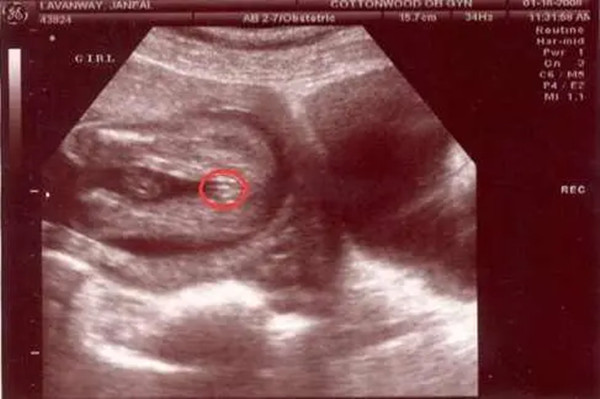

4、看B超图像

怀孕四个月左右,男孩女孩的性器官已经分化完成,此时通过B超完全可以看出男女。男孩的话,B超图像有小突起,就像小jj一样的东东;女孩的话,B超图像是明显的三条线标志。